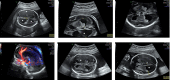

Kinesin super family (KIF) genes encode motor kinesins, a family of evolutionary conserved proteins, involved in intracellular trafficking of various cargoes. These proteins are critical for various physiological processes including neuron function and survival, ciliary function and ciliogenesis, and cell-cycle progression. Recent evidence suggests that alterations in motor kinesin genes can lead to a variety of human diseases, including monogenic disorders. Neuropathies, impaired higher brain functions, structural brain abnormalities and multiple congenital anomalies (i.e., renal, urogenital, and limb anomalies) can result from pathogenic variants in many KIF genes. We expand the phenotype associated with KIF4A variants from developmental delay and intellectual disability with or without epilepsy to a congenital anomaly phenotype with hydrocephalus and various brain anomalies at the more severe end of phenotypic manifestations. Additional anomalies of the kidneys and urinary tract, congenital lymphedema, eye, and dental anomalies seem to be variably associated and overlap with clinical signs observed in other kinesinopathies. Caution still applies to missense variants, but hopefully, future work will further establish genotype-phenotype correlations in a larger number of patients and functional studies may give further insights into the complex function of KIF4A.